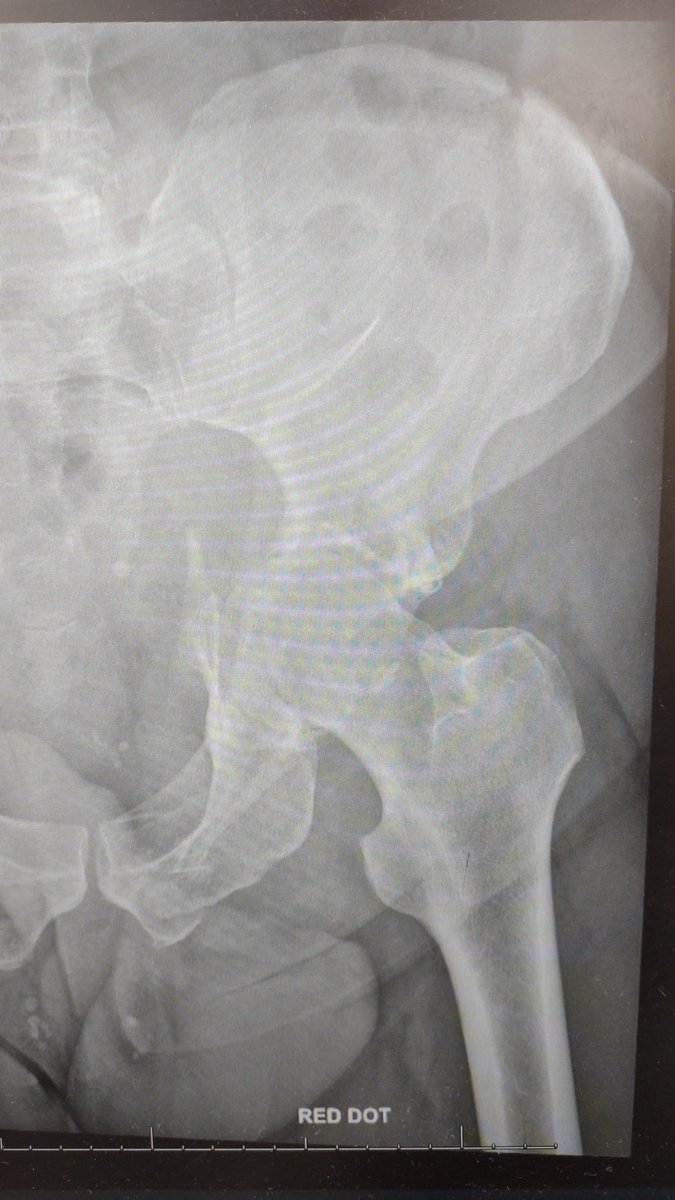

72 year old man, hobbled into the emergency room complaining of left hip pain. What is the diagnosis? #EmergencyMedicine #emergency #doctor #nurse #MedStudentTwitter

72 year old man, hobbled into the emergency room complaining of left hip pain. What is the diagnosis?

#EmergencyMedicine #emergency #doctor #nurse #MedStudentTwitter